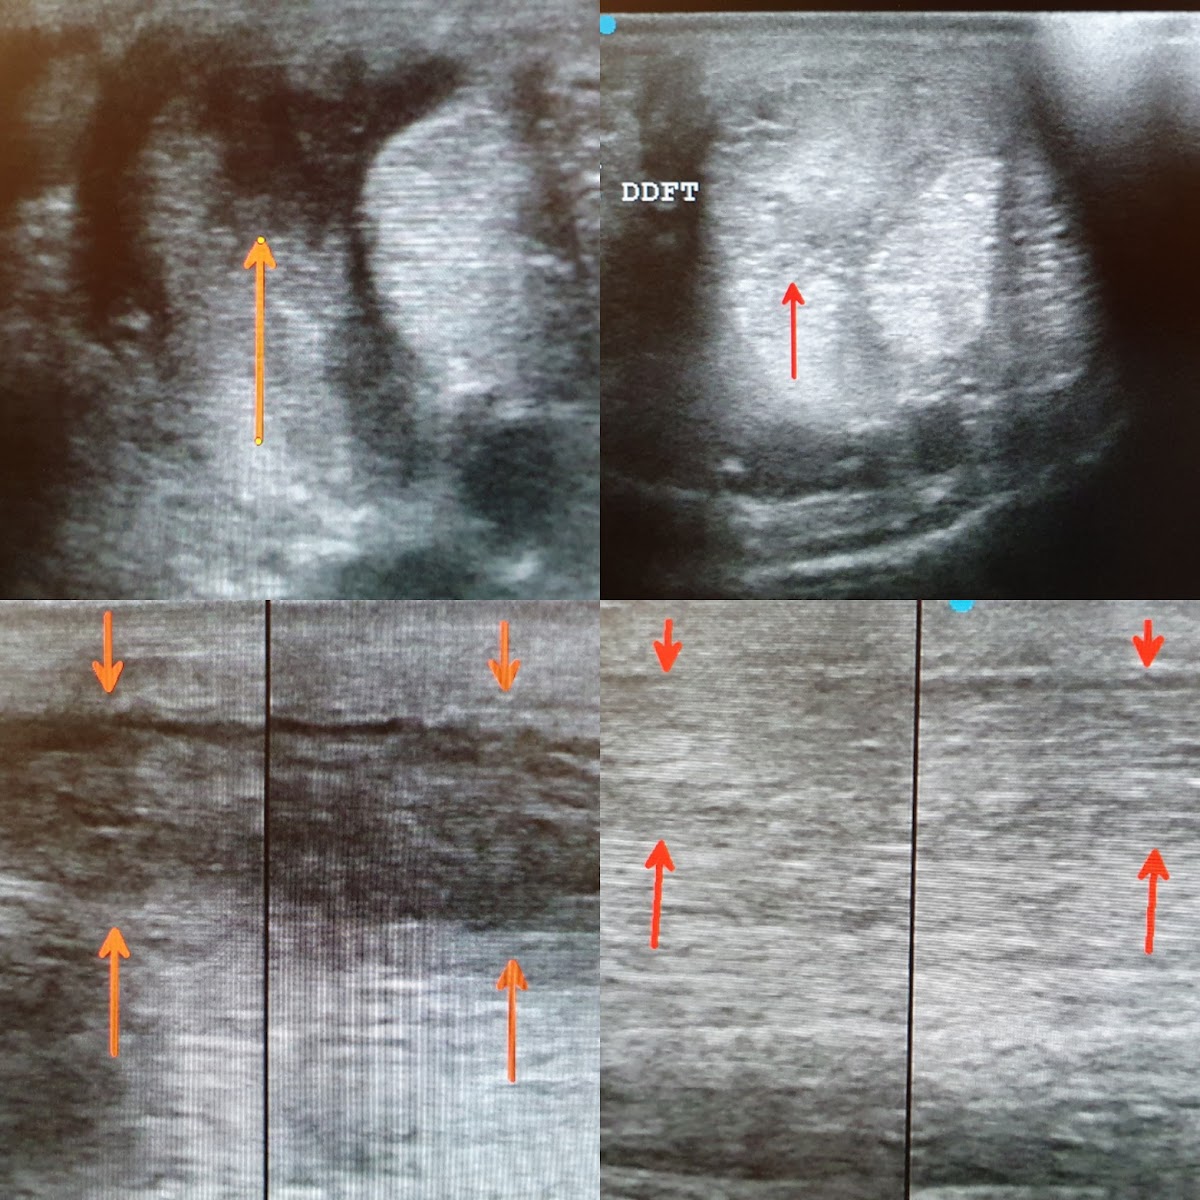

Hatte vor 2 Wochen eine AKU von Herr Dylewski machen lassen. Ich kann ihn absolut empfehlen, er verfügt über ein enormes Fachwissen. Kann alles super erklären, ist sehr ehrlich, sehr genau und macht seine Arbeit äußerst gewissenhaft. Was mir gerade in Hinblick auf Pferdekauf sehr wichtig ist. Ich würde immer wieder Herr Dylewski für eine AKU kontaktieren. Ganz klare Empfehlung! Vielen Dank für die genaue Arbeit und super Beratung!